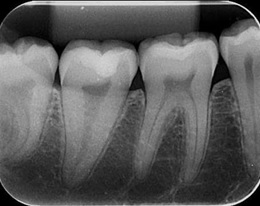

Radiografia Periapical